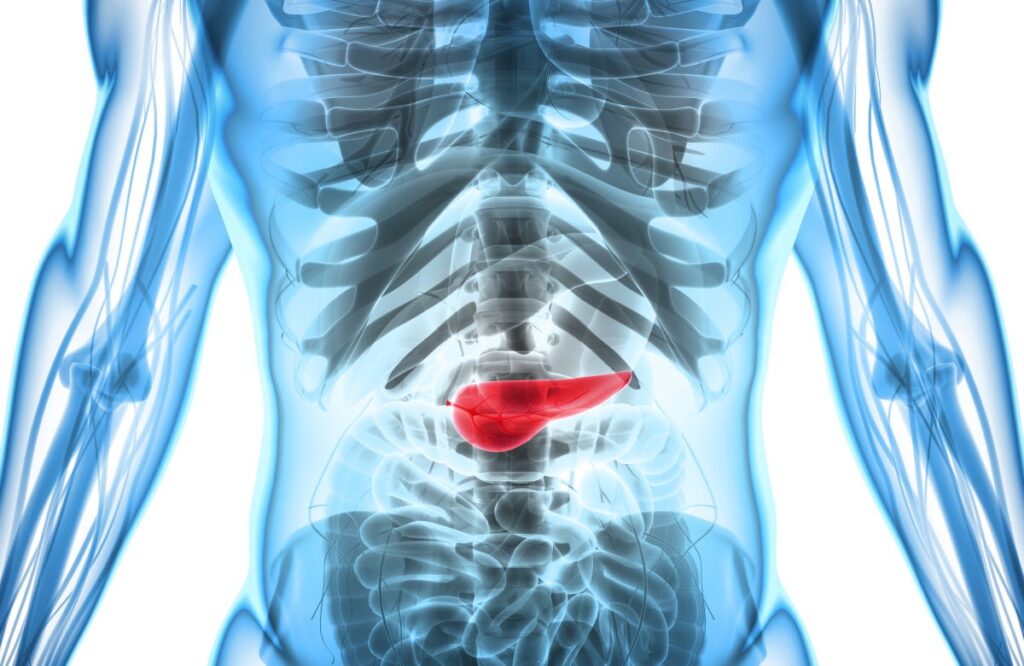

膵臓がんは治療が難しい病気である上に発見しにくく、初期の兆候が見過ごされがちです。その結果、多くの患者は病気が進行した段階で診断されます。ここでは実際の患者の事例を挙げて、膵臓がんの初期兆候を説明し、一般の人の認識を高めていくことができれば幸いだと思います。

膵臓がんの発見されにくさ

初期症状で見つけにくいため、膵臓がんは初期段階ではなかなか発見できません。診断されたときは、がんはすでに周囲の組織や他の臓器に広がっており、手術で取り除くことができない進行がんとなっている事が多いのです。進行した膵臓がんの治療は、症状を管理し、がんの進行を遅らせる化学療法、放射線療法、免疫療法がありますが、これらは治癒を目指すものではありません。膵臓がんが非常に早期に、局部的に発見された場合には、手術が治療の選択肢となり得るのです。

診断5年後の生存率は全患者のわずか12%です。膵臓がんが進行していると診断された患者は、診断後、約1年の生存が一般的です。腫瘍が大きくなる前、または広がる前に診断された場合、平均生存期間は3~3.5年です。早期診断を受けた膵臓がん患者の治癒率は約10%です。

膵臓がんの早期発見は、治療と予後にとって非常に重要です。